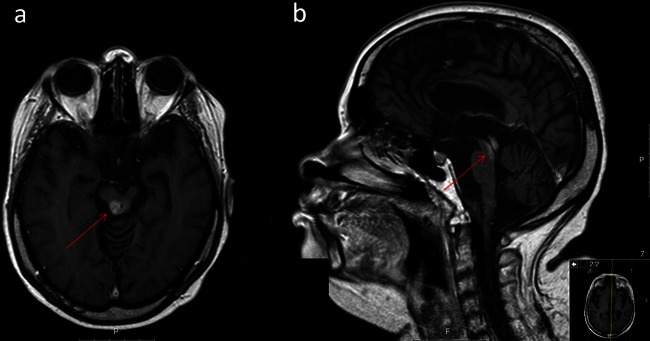

She was admitted for clinical re-evaluation because of motor and cognitive deterioration. She was bedridden, tetraparetic, with severe cognitive impairment preventing any verbal communication, apart from elementary responses. During the first week of hospitalisation she developed persistent elementary vocal tics and swallowing disturbance, often showing facial signs of discomfort. Oropharyngeal examination revealed the presence of continuous rhythmic movement of the soft palate typical of palatal tremor (video 1) which was also present during sleep. No repetitive audible clicks were noticed. Brain magnetic resonance disclosed the presence of lesions involving the dorsal midbrain tegmentum and periaqueductal area without hypertrophy of the inferior olive (figures 1 and 2). Baclofen was introduced with slight symptomatic relief. Palatal tremor, also called palatal myoclonus, is a rare movement disorder characterised by brief, rhythmic involuntary movements of the soft palate. It is presumably caused by dysfunction (essential palatal tremor) or a lesion (symptomatic palatal tremor), involving the Guillain-Mollaret triangle also known as ‘myoclonic triangle’ (dentate nucleus, red nucleus, inferior olivary nucleus and central tegmental tract). Brainstem or cerebellar disorders such as stroke, demyelinating diseases, trauma and tumours are often identified.1There is no established treatment for palatal tremor. Palatal botulinum toxin injections, and other drugs such as clonazepam, flunarizine, baclofen or sumatriptan are used, but these interventions are often unsuccessful.2 3

Figure 1.

Brain MRI showing lesions involving the dorsal midbrain tegmentum and periaqueductal area in axial fluid-attenuated inversion recovery (A) and sagital T1 with gadolinium (B) weighted images.